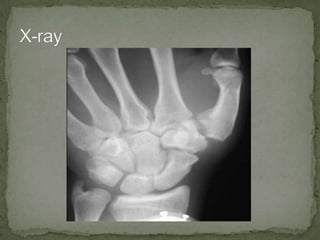

A 30-year-old male presented to the emergency department with right hand pain after punching a brick wall. He has a history of Hepatitis C and heavy alcohol use. On examination, he had tenderness and swelling over the first metacarpal bone. X-rays revealed a Bennett fracture, an intra-articular fracture of the base of the first metacarpal with a triangular fragment. The fracture was treated with closed reduction, thumb traction, and splinting. He was referred to an orthopedist for follow up.